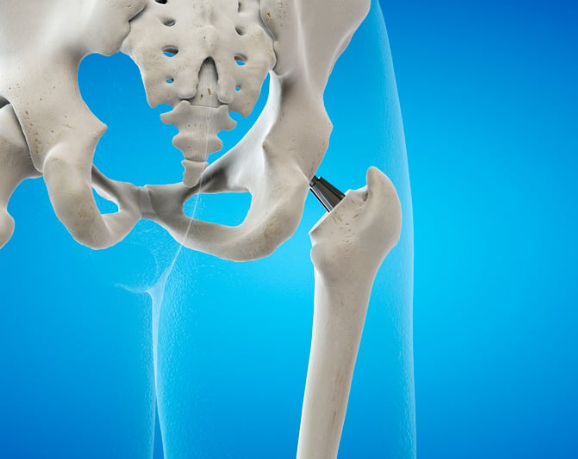

What Is Snapping Hip Syndrome?

Snapping hip syndrome (sometimes called coxa saltans) is when a tendon flicks over a bony structure in the hip, creating a snapping or clicking sensation.

3️⃣ Intra-Articular Snapping

Less common, but more serious.

This involves something inside the joint — like a labral tear or cartilage issue.